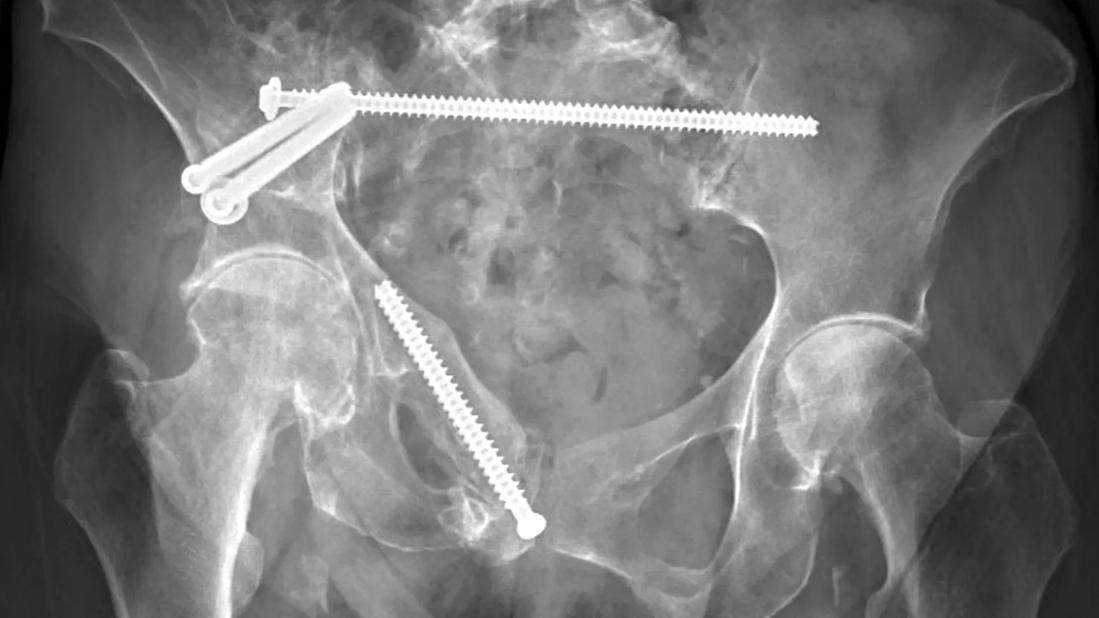

X-ray of pelvic ring fixation

AP pelvis radiograph of a patient eight months after pelvic fixation. Hardware appears stable with previous pelvic ring fractures healed.